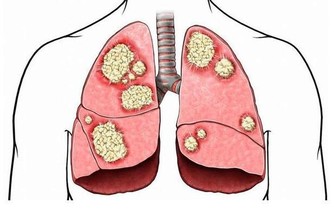

三伏天過去後,夏秋交際的季節,寒溫不調,人體免疫力下降,此時正是肺熱的高發時節,主要是乾咳、痰多、唇部乾燥等現象。

但是,持久劇烈的咳嗽不僅影響休息,還會消耗體力,甚至將病變擴散到鄰近的小支氣管,誘發肺炎、肺氣腫等重大疾病。所以,選止咳藥時,要先弄清病因。

專家提醒,秋季燥熱,傷肝傷脾,表現為咳嗽痰多。